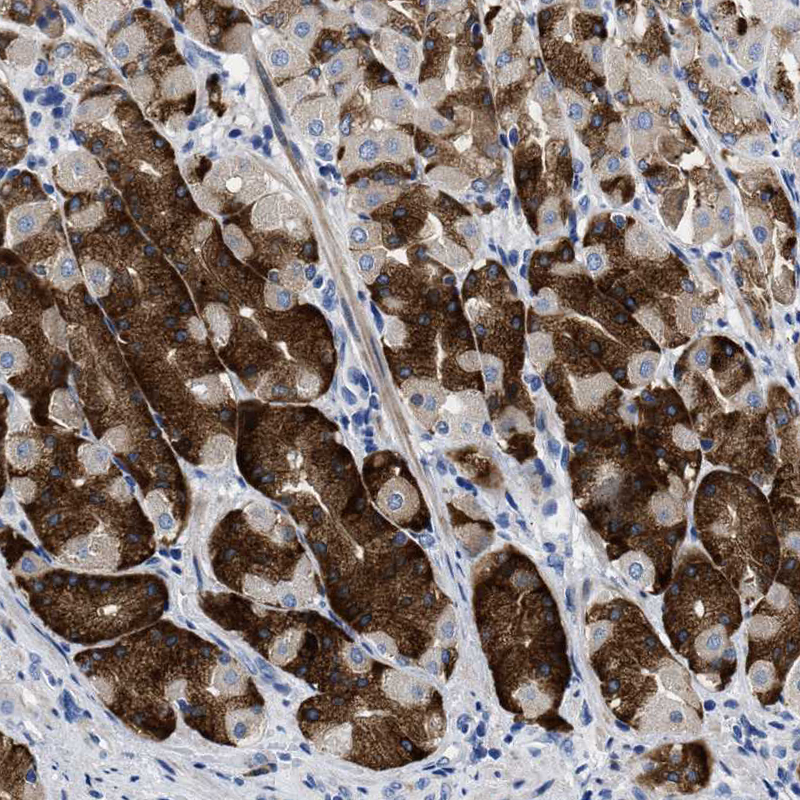

Immunohistochemical staining of human thymus shows moderate to strong positivity in cortical epithelial cells.